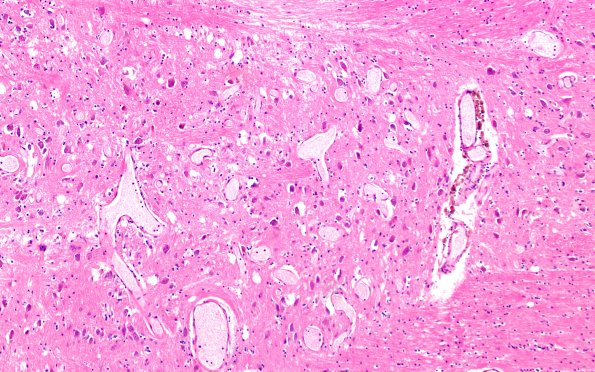

Washington University Experience | VASCULAR | Telangiectasis | 29A3 Telaniectasis (Case 29) 10X

29A3,4 A close-up shows a cluster of thin walled vessels, surrounded by intact pontine neurons, focal deposition of hemosiderin containing perivascular macrophages and absence of reactive astrocytosis. (H&E)